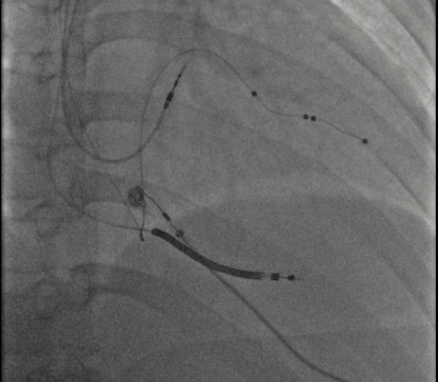

患者收入医院心内科后,给予规范药物治疗;同时,心脏医学中心主任、心脏重症监护室(CCU)主任张俊蒙,会同心内科主任皮林,联合心内科专家围绕患者病情进行讨论,认真分析:患者病情危重,属终末期心衰,且合并冠心病、心律失常,三者互为因果,加重患者症状。经全面评估,决定采用“房室结消融联合永久起搏器植入术”。因患者及家属之前辗转多家大医院,均无有效治疗方案。心衰流行病学研究显示,,心力衰竭患者5年死亡风险近50%,而重度心衰患者1年死亡风险达50%。而这个手术方案无疑给处在绝望的家属一线希望!经与患者及家属沟通,并取得同意后,张俊蒙团队仅用1小时20分即完成难度非常高的三腔起搏器植入术,接着完成房室交界区消融。手术过程顺利,无不良并发症,起搏器程控相关参数良好。

它是由两个手术组成,一个是起搏器植入术,包括普通双腔、CRT(三腔)起搏器的植入。另一个手术是消融房室结(或房室交界区),目的是阻断房室之间的电连接,从而令快速紊乱的房性心律不影响心室的收缩。